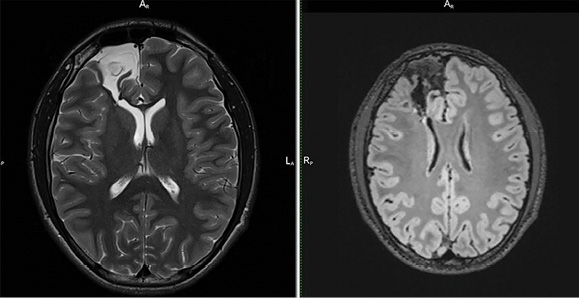

Рисунок 1. Кистозно-глиозные изменения в правой лобной доле. Слева – Т2-ВИ. Справа – FLAIR. Кистозно-глиозные изменения с отложением гемосидерина по периферии.

Figure 1. Cystic-gliotic changes in the right frontal lobe. Left – T1WI mode. Right – FLAIR mode. Cystic-gliotic changes with the deposition of hemosiderin on the periphery.

На современных МРТ используются такие импульсные последовательности, как Т2-ВИ либо SWI, которые способны визуализировать оксигемоглобин даже в минимальных количествах как включение сигнала высокой либо низкой интенсивности соответственно (рисунок 1) [6]. Однако такое программное обеспечение доступно далеко не в каждой нейрохирургической клинике, а сама программа длится не менее 3 мин.